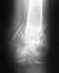

Застарелый разрыв акромиально-ключичного сочленения с расхождением между дистальным отделом ключицы и акромионом до 15 мм.

В сентябре после травмы диагностирован разрыв акромиально-ключичного сочленения. На данный момент сохраняется выраженный болевой синдром при подъеме на 45 град и более и усиливающийся при дальнейшем подъеме,наложена фиксирующая повязка и все.На УЗИ расхождение между дистальным отделом ключицы и акромионом 15 мм, на здоровой стороне до 5 мм, по УЗИ ключица и акромион на одном уровне, ступеньки нет. Имеется разрыв связки. Нужно ли оперативное вмешательство?